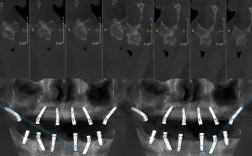

- 适用于单颗牙缺失、多颗牙缺失、全口无牙颌(All-on-4/All-on-6等)等各种情况。

- 尤其擅长处理骨质条件不佳(骨量不足、骨密度低)的病例,以及需要即刻种植、即刻负重的病例,得益于其出色的初期稳定性。

- 提供多种直径和长度的种植体型号,满足不同临床需求。